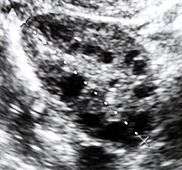

Polycystic ovary syndrome (PCOS) is an endocrine disorder characterized by an excess of androgens produced by the ovaries. It is estimated that approximately 90 percent of women with PCOS demonstrate hypersecretion of these hormones.[6] A concrete cause for this condition is currently unknown. Speculations include genetic predisposition, although the gene or genes in particular have yet to be identified.[7] Evidence suggests that the condition may have a hereditary basis. Other possible causes include the effects from an increase in insulin production. Insulin itself has been observed capable of inducing excess testosterone levels in the ovaries.[8] Elevated insulin concentration in the body leads to lower production of sex hormone binding globulin (SHBG), a regulatory glycoprotein that suppresses the function of androgens.[9] High blood levels of insulin also work in conjunction with ovarian sensitivity to insulin to cause hyperandrogenemia, the primary symptom of PCOS. Obese individuals may be more biologically inclined to display PCOS due to markedly higher amounts of insulin in their bodies. This hormonal imbalance can lead to chronic anovulation, in which the ovaries experiences difficulty releasing mature eggs. These cases of ovulatory dysfunction are linked to infertility and menstrual disturbances.[6][10]